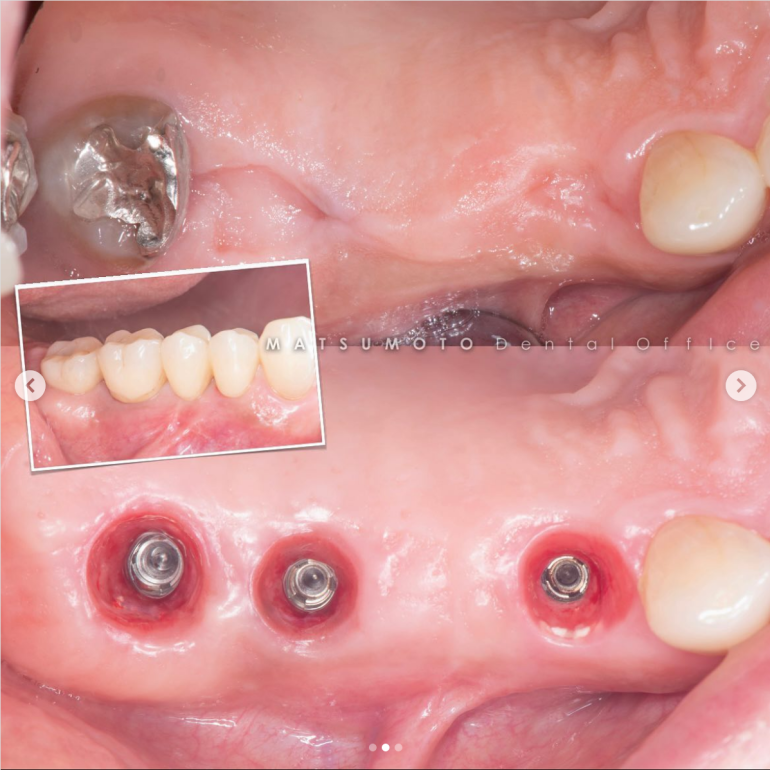

術前写真

上顎:インプラントが不適切な位置に入っており、仮歯を無理やり入れている状態。

下顎:インプラント周囲の骨がなくなっており、保村不可能な状態。

All-on-6を終えて

最終補綴

上顎:ロケーターアバットによる義歯

下顎:フルジルコニアブリッジ

治療のリスクと副作用

治療期間:約半年

治療費:¥3,850,000(税込)

リスク:インプラントのネジが緩むことはありますが、なるべく連結しないような設計にしているので、問題をはやく見つけやすくしております。